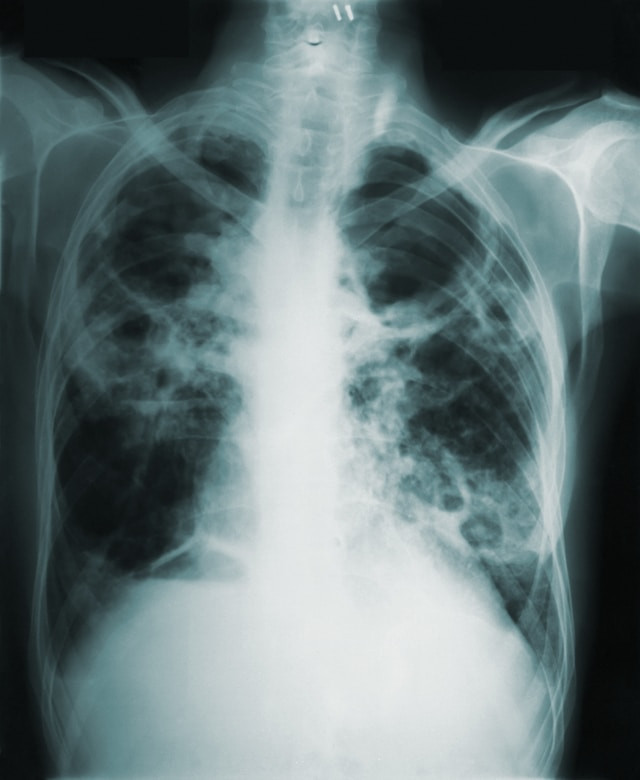

TBC Bukan Sekadar Soal Paru-Paru

TBC tumbuh subur dalam kondisi perumahan padat, ventilasi buruk, dan gizi kurang. Namun faktor-faktor itu tidak hilang begitu saja seiring pertumbuhan ekonomi. Di Jakarta, kepadatan hunian di sejumlah kawasan masih membuat transmisi TBC sangat mudah terjadi. Di luar Jawa, keterbatasan fasilitas diagnostik membuat pasien tidak terdeteksi selama berbulan-bulan.

Ada dimensi lain yang sering luput: TBC resisten obat atau MDR-TB. Indonesia adalah salah satu dari lima negara penyumbang 60 persen kesenjangan antara estimasi kasus MDR-TB dengan kasus yang benar-benar masuk pengobatan (WHO, 2025). MDR-TB lebih sulit diobati, membutuhkan obat lebih mahal, dan masa pengobatan lebih lama. Pasien TBC biasa yang putus obat berpotensi berkembang menjadi MDR-TB, dan pasien MDR-TB yang tidak terdeteksi menjadi sumber penularan yang jauh lebih berbahaya.